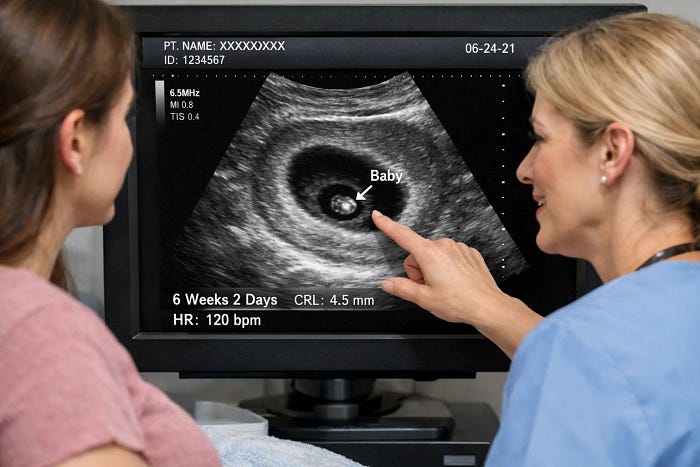

Usually performed around 6–12 weeks, the dating scan and viability scan are the first appointments for pregnant women, when the reality of pregnancy truly sinks in.

The 6-week ultrasound determines how far along you are. It helps calculate your estimated due date, and helps verify the number of babies (so you know if you’re expecting one or more!).

The viability scan is often combined with the 6–12 week ultrasound dating scan in early pregnancy. It helps your doctor confirm the presence of a heartbeat and assess early development to ensure everything is progressing exactly as it should.